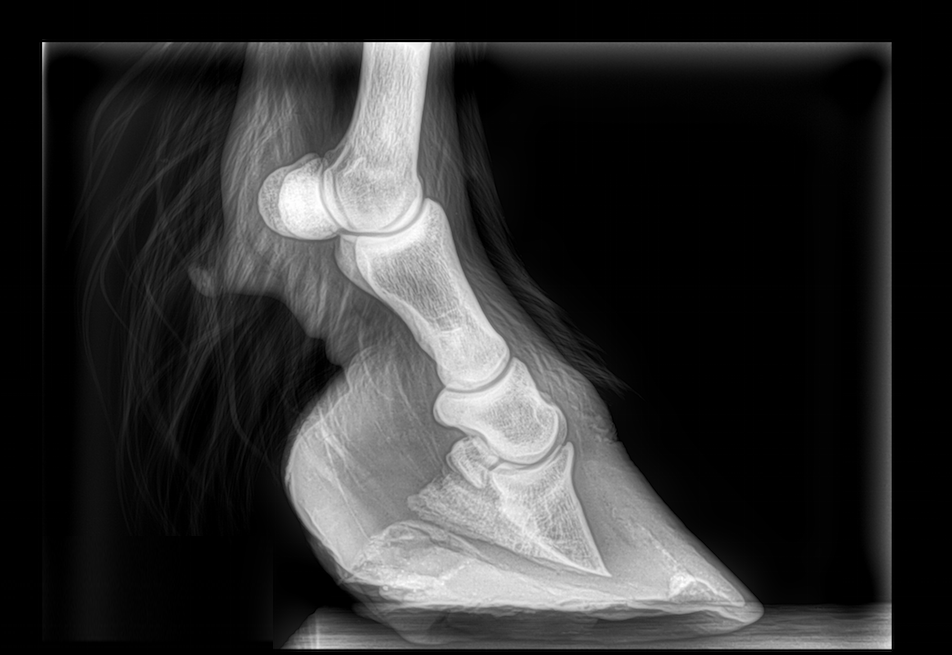

Horse Hoof X Ray Laminitis . Laminitis is commonly divided into three phases: It can occur in any of the horse’s. In the foot of the normal horse or pony, the hoof wall and. laminitis is an extremely painful condition affecting 1 in 10 horses/ponies every year 1 and can cause permanent damage to the hooves. It has significant welfare implications for owners. how is laminitis diagnosed? Laminitis is diagnosed based on clinical signs, although this can be challenging in mild cases. the standard radiographs that should be obtained to aid assessment of horses with laminitis are the lateromedial, horizontal dorsopalmar and dorsal 45°. laminitis is defined as damage to and/or inflammation of the laminae—the tissues that suspend the coffin bone within the hoof capsule. laminitis is a common, extremely painful and frequently recurrent condition in horses, ponies and donkeys. laminitis is a common, painful and potentially devastating condition affecting the feet and hooves of horses and ponies.